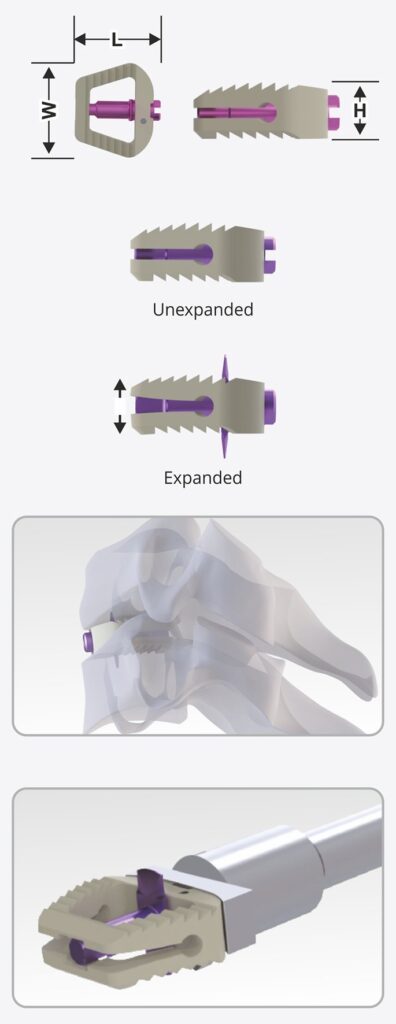

The Stand-Alone Expandable Anterior Cervical Bladed Cage is a next-generation spinal implant designed for Anterior Cervical Discectomy and Fusion (ACDF) procedures. Engineered for superior anatomical fit, this cage combines expandable height technology, integrated anchoring blades, and zero-profile fixation in a single, self-contained device—offering unmatched ease of use, stability, and clinical outcomes.

Size 13 x 15 mm and Lordosis 50

Height: 5mm to 10mm (1mm Variation)

Size 15 x 17 mm and Lordosis 50

Height: 5mm to 10mm (1mm Variation)